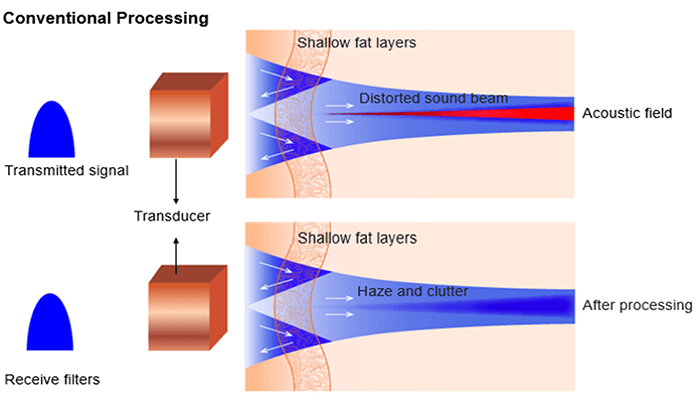

Tissue Aberrations

Harmonic imaging is also used for aberration corrections. Aberration phenomenon occurs when the ultrasonic waves are distorted due to local changes in the speed of sound. Shallow fat and skin layers distort sound beam. It is important to know that distortions are of low energy but send sound in random directions.

As aberrations are also of low energy, they never develop harmonics. Therefore receiver filters tuned at harmonic frequency remove aberrations at f0 and clean up the image.

Clinical Advantages

The advantages of harmonic imaging include, but are not limited to improved signal-to-noise ratio and reduced artifacts, or better axial and lateral resolutions due to higher frequencies and narrower beams.